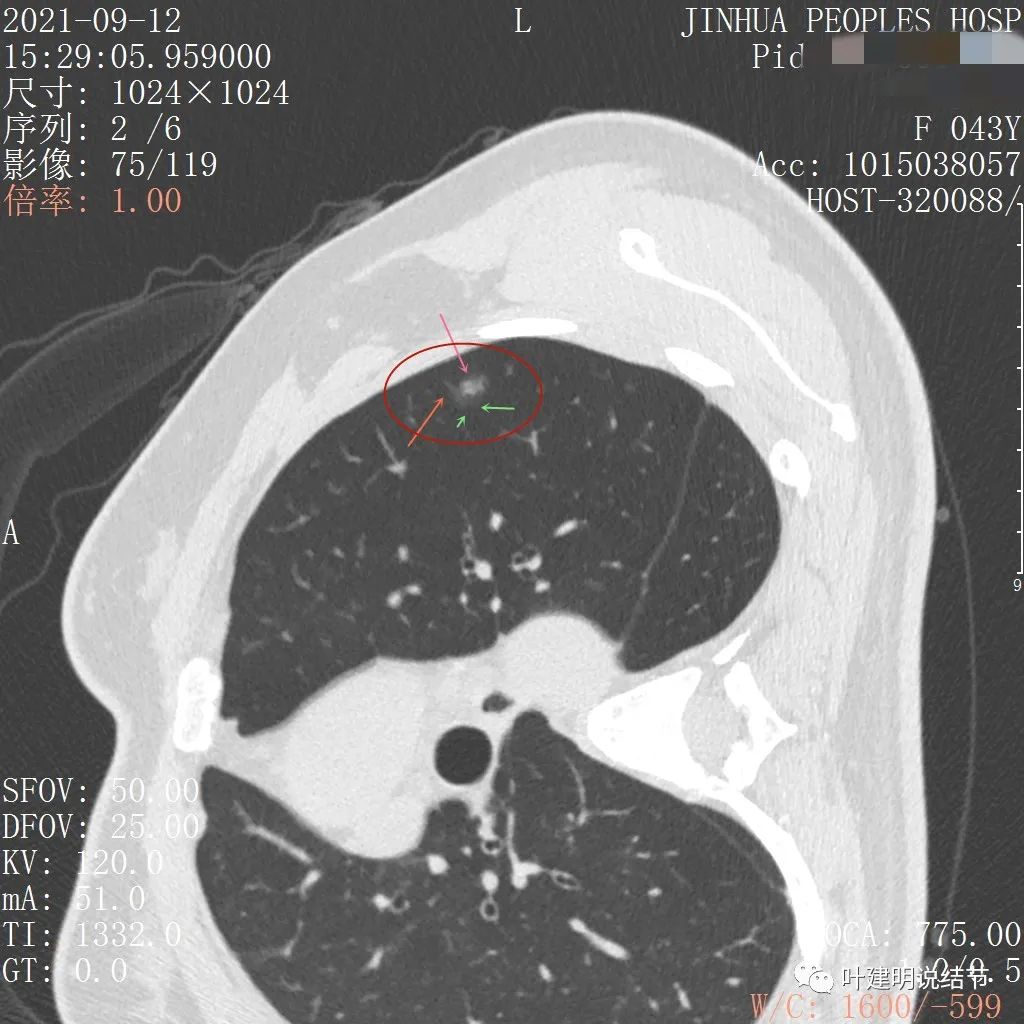

病灶瘤肺边界清,密度偏低,有点散,但有微小血管进入(桔色箭头)

病灶整体密度较低,但轮廓较清,内部密度不大均匀,显得杂乱

不均质的偏低密度磨玻璃结节,轮廓清